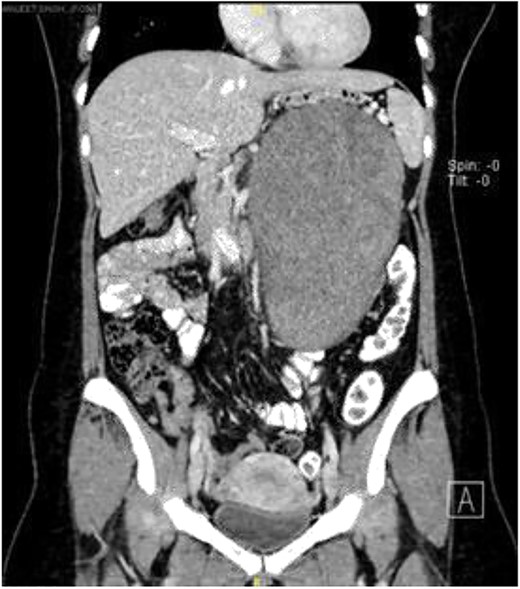

Computerized tomography scan demonstrated a large, well-defined lobulated heterogeneously enhancing solid cystic mass sized 10.7 cm × 12.7 cm × 22.2 cm. The mass displaced the pancreas anteriorly, and it compressed onto the splenic vein with collateral vessels seen, draining into the portal vein. Posteriorly, the lesion displaced the left kidney posteriorly and compressed onto the left adrenal gland superiorly. The remaining structures were unaffected (Fig. 1).

Subsequently, a magnetic resonance imaging was performed to better delineate fat plane with adjacent organs. Similarly, it showed a large left retroperitoneal solid-cytic mass with mass effect and poor fat plane between it and the left kidney, left adrenal gland, splenic hilum and pancreas. Additionally, posteromedially, the mass appeared to be abutting the abdominal aorta at L2 level with poor fat plane in between. Fortunately, no obvious invasion or filling defect was noted within (Fig. 2).